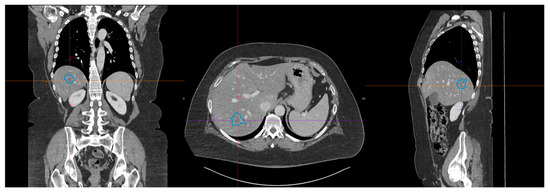

Recent advances in AI-driven medical imaging and analysis are transforming computational bioengineering research and clinical practice, enabling quantitative insights into healthy and diseased tissues. From static imaging- to dynamic video-based analyses, these techniques provide tools for understanding complex physiological processes such as vascular pathologies, tumor hypoxia, neurodegeneration, and fetal development. Imagine modalities, such as ultrasound, MRI, CT, and PET, are at the forefront of this transformation, supported by cutting-edge AI-driven computational methods.

Recent breakthroughs in AI, particularly machine learning, are driving innovations in medical image and video analysis. These include addressing challenges such as motion artifacts, operator dependency, and multimodal integration. We welcome contributions on cutting-edge AI-driven methods and novel hardware/software integrations that enhance medical imaging for diagnosis, monitoring, and therapy, including the following: